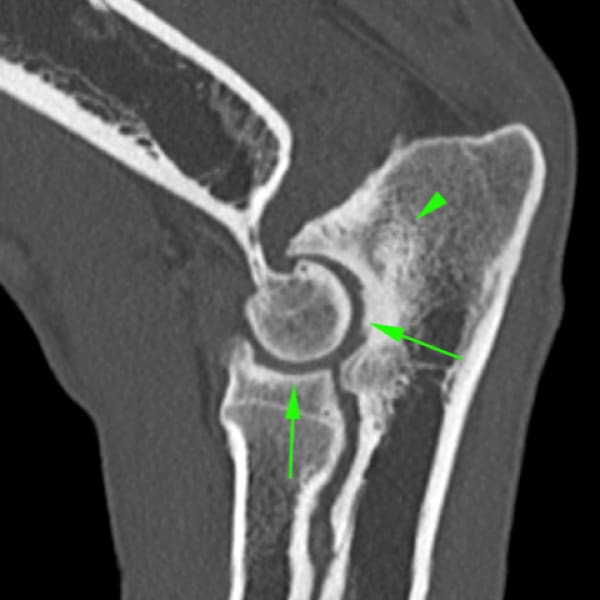

• No unión del proceso ancóneo (NUPA): el proceso ancóneo del cúbito, que en muchas ocasiones posee un núcleo de osificación independiente al resto del hueso, no se fusiona después de los 5 meses de edad. En muchas ocasiones se relaciona con la incongruencia articular.

La Tomografía computerizada (CT) o TAC es la técnica por imagen de elección. El procesado avanzado de la imagen nos permitirá visualizar finos cortes de la anatomía y detectar pequeñas lesiones (por ejemplo, fragmentación del proceso coronoides), las cuales son difíciles de diagnosticar en radiografías convencionales.

• EXTRACCIÓN vs FIJACIÓN DEL PROCESO ANCÓNEO NO UNIDO: La primera opción (extracción) va a generar micromovimientos articulares que pueden favorecer la aparición de roces anormales en el codo. Se optará por este tratamiento cuando dicho proceso ancóneo se encuentre malformado, esclerótico, o en casos donde no sea posible su reducción anatómica. La segunda opción consistiría en la reducción y fijación (osteosíntesis) del proceso ancóneo, la cual se puede plantear cuando la forma y densidad del fragmento lo permitan, y siempre que no aparezcan signos degenerativos o estos sean mínimos. Generalmente cuando se opta por la osteosíntesis del ancóneo, se suele acompañar de una osteotomía cubital que permite que la posible asincronía del crecimiento entre radio y cúbito no interfiera en la consolidación.